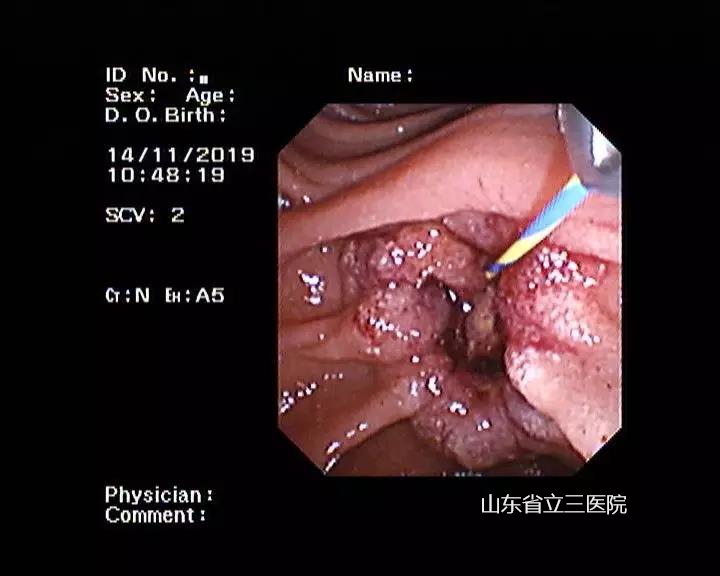

省立三院肝膽外科結(jié)合患者體征特點(diǎn),與患者家屬充分溝通后,在11月14日、15日先后為患者進(jìn)行了兩次內(nèi)鏡下光動(dòng)力手術(shù)治療。手術(shù)過(guò)程中,張锎主任與團(tuán)隊(duì)密切配合,運(yùn)用嫻熟的ERCP技術(shù)將半導(dǎo)體激光插入患者膽總管下段及十二指腸乳頭處,對(duì)腫瘤進(jìn)行照射,并在膽總管內(nèi)放置了塑料支架,保證患者膽汁流出通暢。兩次手術(shù)過(guò)程均迅捷順利,患者術(shù)后快速恢復(fù),2020年1月8日來(lái)院復(fù)查時(shí),發(fā)現(xiàn)十二指腸乳頭腫瘤已經(jīng)壞死脫落,手術(shù)完全達(dá)到了預(yù)期效果。

患者手術(shù)前經(jīng)過(guò)內(nèi)鏡檢查確診十二指腸乳頭及壺腹部腺癌

患者第一次光動(dòng)力治療后

患者第二次光動(dòng)力治療后

在兩次光動(dòng)力治療后放置支架